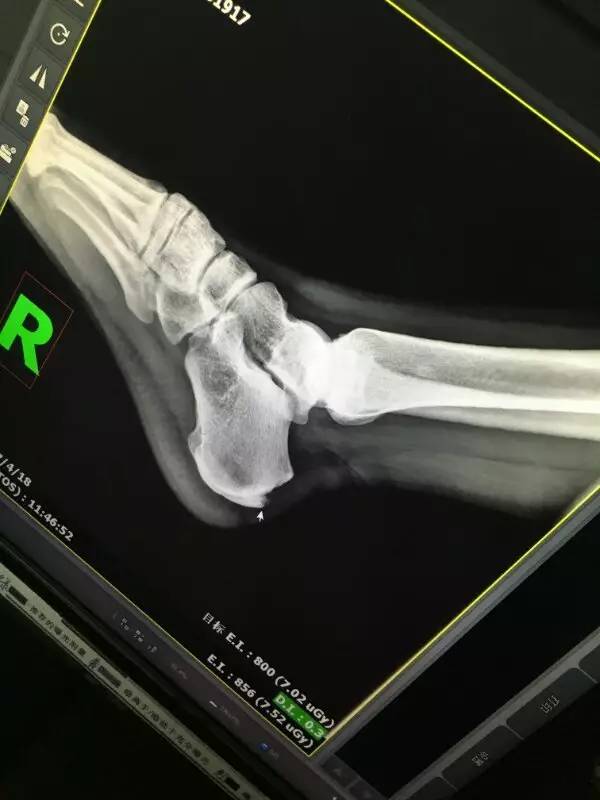

(11)蔡队 齐医生你们好 关注公众号这么久了第一次提问没想到是问伤病的 如图所示 左小腿内侧踝关节上面点画圈那个地方 按着的时候有很强烈的疼痛感 然后打球的时候一旦用力或者受力的话也会感觉到疼痛 不过这种感觉时有时无 持续好几个月了 我想知道是不是里面的韧带损伤了还是怎么回事儿 有什么治疗的方法 可以痊愈吗

----去医院拍片,要严防胫骨疲劳性骨折。